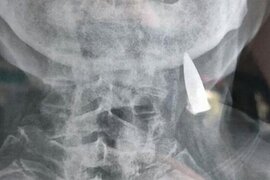

Baş ağrısı şikayəti ilə həkimə gedən 95 yaşlı kişinin rentgen nəticələri həkimləri şoka saldı

Çinli 95 yaşlı Zhao He adlı kişi 25 yaşında İkinci Dünya Müharibəsinə qatılıb. Müharibə zamanı bədəninin bəzi nahiyələrindən güllə yarası alan şəxs bu güllələrin onun bədənindən çıxdığını düşünsə də, həqiqət bu cür olmayıb. xarici mediaya istinadən xəbər verir ki, 95 yaşlı Zhao He baş ağrısı şikayət